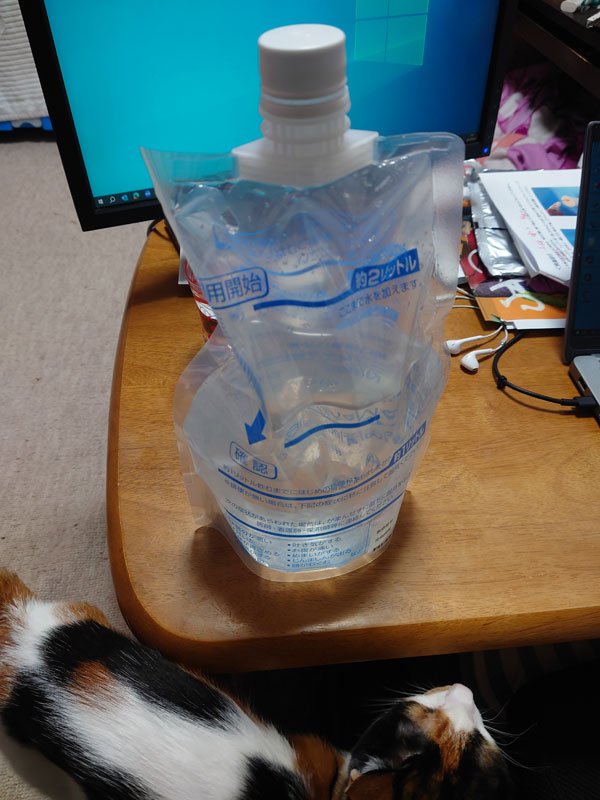

いるさっここにひとりな! 1月からかー。溜めちゃったな。 1月23日(木) 軽い会社の飲み会がありましたが、1月のはじめに腸をやらかしたせいで☆まっちはアルコール抜きでした。 25日(土)  27日(月) 水を飲む前川。  28日(火) 横浜にある某エージェントへ上司Hと一緒に訪問してきました。 手土産くらい課長決裁で領収書切れたらいいのに、細かい会社です。 せっかく横浜まで来たので、上司Hと軽く飲んで帰りました。 ※この時点でも☆まっちはアルコールNGでウーロン茶だったはず 横浜シュウマイ買って帰りました。 30日(木) 外部セミナーに参加してきました。 最近こういうセミナーによく参加しています。  2月1日(土) こずへ氏からもらったメスティン使いました。  家の中でキャンプ飯を作ります。  完成。  2日(日) 孤独のグルメ劇場版を見るために、亀有へ行ってきました。  商業施設の中のゲームセンターなんですけど。  そうとは思えないほど凝った作りでした。  孤独のグルメ劇場版はけっこう良かったです。 序盤は唐突な展開の連続で不安になりましたが、ちゃんと孤独のグルメでした。聖地巡礼できない構成になってるのは意図的ですかね。 遅めの昼食は亀有メンチという店で。 駅前の賃貸不動産をチラ見しましたが、ぜんぜん下町って感じの価格帯ではなかったです。便利そうでいいですね亀有。  8日(土)  世界平和のために安眠する前川。  9日(日) こずへ氏を誘って、ワンフェスに行ってきました。 初参加です。  午前中は何か入場でトラブルがあったらしいですが、☆まっちとこずへ氏は午後から入場できる一番安いチケットで入ったので無問題でした。 お目当てがあったわけでもなく、雰囲気を見てみたかっただけなのですよね。 幕張メッセの全館を使って実施していたのですが、こういうR18はホール1つぶんの1/3~1/4程度の区画で、イベント全体からするとかなり小さいエリアでした。        島中は全部見切れてないけど、一応全ホールはぐるっと回って、満足して帰りました。早めの晩ご飯も海浜幕張で。  コミケに比べると出店側も参加者も平均年齢が高かったかなという印象です。もちろん普通に子供連れのファミリーもいましたけど。 二次創作はコミケ同様に、流行りものから根強い人気を持つ作品、様々でしたが、数的な偏りとして、妙にゴジラの展示が多かった気がします。造形やってる人が好きなジャンルなんですかね? 13日(木) 会社の飲み会でした。 ランチもやってる会社近くのそば屋さんです。 営業の課長を採用メンバー4人で囲む会でした。  14日(金) ハルト氏からバレンタインのチョコが届きました。  これは☆まっちで暖をとる前川。  15日(土)  16日(日)  18日(火) ☆まっちのマンションのエレベーターが故障して、階段オンリーになりました。 これ、すぐ直るだろうと思っていたら、ちょうど一ヶ月壊れっぱなしだったんですよね…階段で4階なのでけっこう不便でした。Amazonの配達員もけっこう可哀想でした。マジで家賃交渉しようかと思いました。  この日は仕事で横浜ビジネスパークへ行ってきました。再就職支援向けのイベントに同僚H氏と一緒に参加してきました。 22日(土) 池袋でサクラ氏のプレゼントキャンペーンに当たった絆カードの受け取りと、トレードをしてきました。  おまけにバレンタインのチョコもつけてくれました。 ☆まっちもお茶菓子をカウンターできるよう用意していたので事なきを得ました。  それから秋葉原に移動して、CARNELIAN版画展へ。 顔のない月リメイクのこともあり、行ってみたくなったのでした。  23日(日)  前川のサブシステム洗浄に行ってきました。  24日(月)  英傑大戦の配信内で日本統一して旅人に昇格してきました。 ここからが本当の地獄なんですよね……  27日(木) 会社で小規模飲み会でした。 確か☆まっちの研修が終わった後なので出社人口が多かったので行ったのだと思います。  28日(金) これは可愛い前川。  3月1日(土) 大腸憩室炎の最終話です。 うしろの穴から胃カメラを入れて事後検査する日が来てしまいました。 午前中からこれを飲んでトイレ行ってを繰り返さないといけません。  午後から胃カメラを入れて、検査してきました。 カメラの映像はリアルタイムで☆まっちも見られる体勢だったので、自分の大腸や小腸を鑑賞することができました。なかなか経験できない、貴重なアトラクションです。 検査終盤にポリープが見つかったので、それの除去をする時がゲームみたいで草でした。(しかしそのせいでしばらく食事制限がかかってしまった) 結論、特に異常なし。ガンなどでもなし。 最後に☆まっちから、クローン病の可能性なかったか? と聞きましたが、 「全然ないです!」と言われました。 10年越しの呪いが解けたような感じがしました。 敢えて再検査せずに過ごしてきましたが、思い過ごしだったようです。 3月9日(日)  12日(水) 下から見上げた偉そうな前川。  14日(金) 仕事終わり、会社の同僚K氏と越谷レイクタウンの焼肉に行ってきました。  見てくださいこの厚切り牛タン。 これが食べ放題という神コースが飲み放題込みで7000円です。 満足度の高い焼肉でした。また行きたい。  これは☆まっちのケツと前川。  15日(土) 赤羽まで行ってきました。 翌日英傑大戦のイベントがあったのですが、そのために遠征してきていたホッピー氏と連絡を取っていたのです。 直接会ったことはないのですが、☆まっちが大戦組という英傑大戦コミュニティで書いた記事を参考に同じデッキを使ってくれていた方で、ちょいちょいSNSで交流している方でした。 GiGO赤羽の配信環境はそこそこという感じでしたが、記念にゲスト配信してもらいました。 一方、同時刻たまたま秋葉原で遊んでいた飯だぞ氏ときゃろ氏が、☆まっちが配信を始めたのを見て赤羽まで来てくれたのが草でした。 きゃろ氏にもゲスト出演してもらって〆る配信となりました。 16日(日)  18日(火) 同僚N氏と業後に飲みに行きました。 会社周辺で新規開拓した店なんですけど、美味しかったです。 アヒージョにバケットなのに焼きサバやしじみ汁と変な組み合わせですが、けっこう良い店だったんですよ。  21日(金) 会社でエンジニアを集めて懇親会やりました。 企画側だったので一苦労でした。 これは終わった後、同僚のK氏、N氏と食べにいった店。  23日(日) 小喬ペロペロリーダーの真沙さんと配信してきました。 真沙さんが転職で一時的に無職になってしまったので、だいぶ時間に余裕があるようです。 北海道にも旅行に行かれたそうで羨ましい限りです。 これは配信後のラーメン。  24日(月) ☆まっちの膝でくつろぐ前川。  夜に虎ノ門ヒルズで人事交流会に参加してきました。 前々職の会社の人とか来てたり、次の商談に繋がる大学の偉い人と名刺交換とかできて有意義でした。  27日(木) 大手町の人事交流会に参加してきました。 こっちは一応有料だったのですが、内容イマイチでした…  28日(金) 朝一で動物病院に行ってきました。 ちょっと記憶がおぼろげなのですが、ゲロを吐くことが多いので検査してきたはずです。 レントゲンを撮った前川。白いのがサブシステムです。   結論、色んな検査をしたのですが問題ないという結果でした。 けっこうな頻度でゲロしてたので不安だったんですよね。 これは早く帰りたい前川。  30日(日) すえっち氏、こずへ氏とCLANNADの聖地巡礼に行ってきました。 桜の開花時期になったら絶対行こうと去年思っていたのですが、唐突に思い出して2人を誘いました。 Afterまで全話視聴して参戦したノリノリのすえっち氏。  午前中は田園調布、午後から羽村駅周辺を回収することになったのですが、まずは田園調布で桜坂の回収です。                   田園調布はこんな感じで、桜坂の橋がフレームに入るカットの回収が中心となりました。 現実はここから羽村駅へ移動します。 厳密には羽村駅から箱根ヶ崎駅周辺までCLANNADの聖地スポットが点在しているため、羽村駅で下車してから、箱根ヶ崎駅まで歩き、さらにその北まで徒歩で移動することになります。                                     作品全体で登場する桜坂は印象的なスポットですが、桜が咲く季節が少しソメイヨシノとはずれるようです。ぜんぜんつぼみだったので、こちらでは桜が見られなかったのが少々残念でした。 展望台みたいなところまで登りましたが、なかなかの距離を歩いたのでおっさん3人で疲れました。 まだ日が高かったので、立川あたりで解散して晩ご飯は別々となりました。 ちなみに昼食は、羽村駅周辺にある「ふるいち」というラーメン屋で。 これも巡礼サイトで紹介されていたので、ガイドに従って食べてみました。  4月4日(金) 暗いところが好きな前川。  上司Hと課長Hの2人に誘われて飲みに行ってきました。 課長Hが人生楽しそうで何よりですが、まあとにかくエネルギーの高い人で部下は大変だろうなと思いました。 お店は味噌をメインにした様々な食事が出てくる居酒屋でした。良かった。  5日(土)  暫定6歳の誕生日を迎えた前川。 これは新しい寝床。  6日(日)  10日(木) ☆まっちの腕をつかんで離さない前川。  11日(金) 同僚のD氏と一緒に成蹊大学を訪問してきました。 ところが朝から遅刻しかけてこいつマジかよと思いました。  食堂が大きく分けて3つあって、品揃えも豊富でした。 大きい大学です。 久しぶりの学食でテンション上がりました。  夜は会社の飲み会で、主にバックオフィスの集まりでした。 二次会がカラオケで、☆まっちからするとコロナ明けて初という久しぶりのカラオケになりました。 12日(土)  19日(土)  20日(日)  24日(木) スヤスヤの前川。  25日(金) ビッグサイトでJapan IT Weekに出展してきました。 3日連続なのですが、最終日だけヘルプで呼ばれました。 ☆まっちにとって1社目にいた営業の方が歩いててびっくりしました。 もう50代のはずですが、東京に転勤になっていたようです。  終わった後は新橋まで移動して打ち上げでした。 営業陣の参加者が多く、話したことのない営業とも会話できました。 26日(土) 仕事で名古屋のエージェントで担当してくれているH氏と焼肉に行ってきました。 たまたま先方の総会があり、東京出張で来ているという話だったので、☆まっちから接待するつもりで誘いました。 店員さんが全部焼いてくれる系の店です。場所は西麻布だったはず。 駅から歩くので、タクシーで品川まで送り、さらに2軒目を品川で寿司食べて解散しました。 過去一接待で金使ったかもしれん。 でも若くて優秀な方でした。  27日(日)  28日(月) 仕事で、営業同行してきました。 場所が鎌倉の僻地で、そのまま江ノ島まで行きたくなる小旅行でした。 29日(火) 祝日。 飯だぞ氏が配信するというので、秋葉原に来ました。 しかし絵師100人展に初めて来てみました。 まあ良かったですが、撮影禁止だし物販は欲しいものないし、高かったなーという感想でした。 タペストリーグッズもっと作ってほしい。  配信後、晩ご飯は少し歩いたところのラーメン屋へ。  30日(水) 置物のふりをする前川。  5月3日(土) 真沙さんとキャンベルさんと英傑大戦の配信して、牛角でご飯食べてきました。(キャンベルさんは配信終わりで帰ったので2人で行きました) 近況報告など。  5日(月)  6日(火) 自由な前川。  秋葉原で真沙氏、きゃろ氏と英傑大戦の配信してきました。 ゴールデンウィーク、小喬ペロペロのオフ会2回しか予定がなかった☆まっちでした。  打ち上げは温野菜で。  7日(水) ご満悦な前川。  10日(土) 結婚記念日で、親から牛タンが届きました。 翌日晩ご飯で食べたんですけど、めっちゃ1枚が大きくてびびりました。 牛タンとご飯だけで十分でした。 柔らかいし、なかなか良い牛タンだったんじゃないでしょうか。  赤羽で二次裏のオフ会行ってきました。 いいちこ氏が単身赴任で東京に来ていて、その歓迎会がメインでした。  11日(日)  12日(月) 這い寄ってくる前川。  13日(火) 春の陽射しで光合成する前川。  15日(木) 大崎でセミナー出てきました。 名刺交換会の方がメイン目的でしたが、割といいセミナーでした。  16日(金) 会社でエンジニアを集めて懇親会やりました。 運営側だったのでやっと大きい仕事がひとつ片付いた感覚です。 18日(日)  20日(火) 朝の始まりを教えてくれる前川。  22日(木) 採用メンバーのF氏、N氏、K氏、新卒チームのK氏も含め、代々木周辺で飲んできました。 この会社入って飲み会増えた気がします。  23日(金) 渋谷で取引先との懇親会でした。今回は先方から誘われたので、接待受ける側でした。 大阪で知り合ってから長い付き合いのS氏ですが、出世を繰り返して今では今の事業部でトップ4くらいまで偉くなったそうです。ベンチャーは出世も早いですね。 その部下2人を連れて来てくれたのですが、なかなか楽しかったです。  25日(日)  動物病院へ。 サブシステムの定期洗浄です。  鎮静剤みたいなのを打つようで、帰ってきてからもウトウトしてました。  30日(金) 午前休を取って浜松町の病院と、新宿のUFJに行ってきました。 病院はただの定期でウルソの処方を貰いにいっただけですが、UFJは甥っ子の結婚式のためのピン札を作りに行った感じでした。 フレックス11時出社でも間に合ったのですが、銀行がどれくらい待たされるか分からなかったので午前休を取った感じでした。 ちなみにいくら包むか姉とショートメッセージでやりとりしていましたが、名古屋人の見栄っ張りを感じました。 親族とはいえ、10万でも一般的に十分ですよね? 姉一家は4人家族で出席するから倍出すとか言ってました。 夜は採用メンバーで飲み会。 以前、N氏とさし飲みで来た店を使いました。 N氏、K氏、K氏、あとメインどころだったD氏が普通に仕事入れてたせいで遅刻して参加。 みんないろいろ我慢しているようで、サラリーマンだなって思いました。  31日(土)  6月1日(日) 飯だぞ氏を誘って、柏駅からちょっと歩いたところにある洋食屋さんに来ました。 これが400gのポークステーキです。めっちゃ柔らかくて美味しかったです。  5日(木) 自宅警備をする前川。  夜は営業のI氏とエンジニアのK氏の対談企画を行いました。 K氏がクッソ優秀な経歴かつ人柄も良くて感動しました。 6日(金) 有休を使っていました。 ☆まっちとEK氏、二人とも出かける準備を始めて、危機を察知する前川。  観念してペットホテルに預けられる前川。  甥っ子の結婚式が名古屋なので、前川を預けたら一路新幹線で名古屋へ向かいました。 ホテルは美容院の近くに取っていました。 夜コムテックタワーに行ったら、E・HERO氏が配信中でした。 あと大阪から遠征して来ていた氷姫氏もいました。 ちょうど式当日が英傑大戦の名古屋キャラバンと被ってたんですよね。 遠征組が名古屋に集まってるので、コムテックタワーの8台はずっと埋まりっぱなしで大盛況でした。 7日(土) 朝からヘアーセットのため2人して美容院へ。 名古屋駅からシャトルバスで会場まで向かいました。 けっこう雰囲気重視というか、森の中で緑豊かなチャペルでした。  屋外で記念撮影をして披露宴会場へ。 どうも1日1組しか対応していない会場らしく、スタッフが多かった印象でした。 披露宴は姉の一家4人と☆まっち、EK氏が同じ卓でした。  兄が新郎の父親になるわけですが、10歳以上離れてるのに兄も姉も良い歳の取り方してるなと思いました。 さすがに記憶の中の20代、30代よりは老けましたが、無様に太ってしまったのは☆まっちくらいのようです。 あと姉の旦那さんが同業のベテランなの初めて知りました。 あとは特にトラブルもなく、帰りもシャトルバスで名古屋へ。 EK氏とは名古屋駅で別れ、☆まっちはもう一泊させてもらいました。 そこから☆まっちは大須観音へ。 英傑大戦の二次裏勢が名古屋キャラバンに集まっていたので、夜のオフ会だけ顔を出してきました。 えっとろ氏、やむーちょ氏、炭素氏と4人の小規模オフでしたが、現住所が全員バラバラというのがイベントという感じがします。 お店は地元民やむーちょ氏のオススメへ。肉野菜炒めをいろいろ味変しながらたくさん食べられる店でした。  それにしても店の入り口が特徴的すぎて草でした。  8日(日) 名古屋で追泊したのですが、この日も大須スタートでした。 大須に宿をとれば良かった。 この日はハルト氏と待ち合わせて、メダリストの聖地巡礼をしてきました。 まずは大須にある名古屋スポーツセンター。       入場して、靴のレンタル&履き替えるためのロッカールーム。     スケートリンクに併設された休憩室。     スケートリンク周辺。     名古屋スポーツセンターのメダリスト広告はこんな感じ。    大須で昼食を採って、大須観音の境内へ向かいました。        これは大須観音の側にある中警察署 大須交番。   大須商店街の北側にある裏門前公園。   そこから地下鉄で港区役所駅まで移動。 もうひとつのスケート場へ向かいます。   駅から少し歩くと邦和みなと スポーツ&カルチャーがあります。               邦和みなと スポーツ&カルチャー内のメダリスト広告(?)はこの通り。      最後に、ららぽーと名古屋みなとアクルスへ歩きます。     歩き疲れたので、中に入ってパンケーキの店でお茶しました。 帰りはタクシー使いました。 そういえば前々職で長い付き合いになった大阪のK氏が退職していたと教えてもらったので、LINEを飛ばしてしまいました。 5年前から虎視眈々と計画しての転職だったらしく、他社で通用するか? みたいな上昇志向が彼にもあったようです。 久しぶりにLINEで話してほっこりしました。 そしてそのまま帰宅。 EK氏が午前中にペットホテルから前川を引き取ってきてくれていたので、疲れ果ててぐったりしてました。  9日(月)  11日(水) 大崎でIT系のセミナー&交流会に行ってきました。 13日(金) ブルアカ4周年合わせで販売された☆画野朗のアクリルボードが届きました。 生きてて良かった。  14日(土)  エアコンの下で脱力する前川。  15日(日) 英傑大戦のグッズキャンペーンが始まったので、土曜と日曜、配信で散財してきました。 とりあえず右のデスクマットをゲット。  これは添い寝してくれる前川。  20日(金) フレックス退社して、親会社の採用チームとの親睦会に行ってきました。 場所が溝の口でちょっと遠かったんですけどね。 同僚のF氏は楽しそうでしたが、大きい会社で大量採用してるぬるい組織って感じはしました。 予算があって採用基準も低けりゃザコでも採用はできる性質の仕事なので、どうも会話の土俵が違うような感じはしました。 21日(土)  近場のラーメン屋に行ってきました。 youtubeで近場の有名店として紹介されていたので行ってみたんですが、炎天下なのに20人以上並んでて、日焼けしました。 お水や日傘まで用意してあって至れり尽くせりです。  思ったより濃い目の味付けで、リピートするほど好みではありませんでしたが… まあ人気なのは分かるような気がしました。  昼は秋葉原まで行って、しゅばるつ氏と絆カードのトレードをしてきました。 最近GiGOアプリを入れてから、そのサービス券が美味しくて。 GiGO以外の店舗でプレイするのが損だとすら感じはじめちゃったので、秋葉原は早々に撤収して柏GiGOで引き続き遊んできました。 22日(日)  23日(月) 寛大な準にゃんに甘える前川。  24日(火)  26日(木) 夜、サポーターズ主催の人事交流会に参加してきました。  前職の上司だったK氏が来ると聞いていて、久しぶりに会ってきました。 (たまたま当日K氏の誕生日だったので、お茶菓子を渡しておきました) ☆まっちの後任として入った人、☆まっちの後に辞めたM氏の後任として入った人、2人の人事担当も来ていて、いろいろ近況など話せました。 つい最近、役員の方がスポーツの事故で亡くなったという話を聞いてびっくりしました。 あと、偶然2社前の先輩? も来ていて、声をかけられました。 ☆まっちが2社目に入社したとき、東京で採用組織のマネージャーだったS氏です。相変わらず相手の顔色を伺うキャラでほっこりしました。 あとは業務的にもほどよく役に立ちそうな名刺交換ができて、無料参加でこんな交流会があるなら、有料の交流会出るメリットないなと思いました。 28日(土)  29日(日) スペシャルグッズキャンペーンの都合でGiGO柏に入り浸っていたので、配信外ですが義士に昇格しました。 7月で大型バージョンアップなので、まあここが最後の昇格でしょう。  |

まあコピー本でも書いたんだけど、日記で時系列で見ていこうか。 ほんとコミケ参加もできるかどうかという年末だったのだよ。 9月30日(月) 前川の定期健診でした。 そういえばこの時は、なんともなかったんですよね…  4日(金) LINEギフトで貰っていた誕生日プレゼントが届きました。 ハルト氏より。  じょにぃ氏より。   10月5日(土)  10月6日(日)  7日(月) 自宅警備に精を出す前川。  8日(火) ホットカーペットの上で野生を忘れる前川。  10日(木) 会社で営業O氏のおかげで、エンジニアのK氏とミーティングができました。上司Hと一緒に夜飲み会もしてきました。 オフィスから少し歩きましたが、O氏の希望により餃子のお店に。 帰りに上司Hから11月からの体制を聞かされて大変だなーと思いました。  10月12日(土)  13日(日)  14日(月)  エアコンの下でセンシティブを背負う前川。  17日(木) EK氏の誕生日前夜だったので出前で良い寿司食べました。  19日(土) EK氏の誕生日に、乾燥機を置くための台を買ったのですが、それを組み立てていました。 なかなかパーツが大きい&重くて苦労しました。 乾燥機本体は高いので家計で買うのです。  前川のありがたいポーズ。   25日(金) 仕事で初めて幕張メッセに行ってきました。 自宅からの乗り継ぎがアクセス良くてびびった。  この日はけっこう大変で、 夕方までほとんど立ちっ放しのイベントのお手伝いをしてから、同僚のK氏と一緒に新宿まで移動。☆まっちメインの研修会を実施して、そこから☆まっち幹事の懇親会でした。 金曜日ということもあり、めちゃめちゃ疲れました。 26日(土) 二次裏オフ会で川崎まで行ってきました。 川崎駅の上にあるビアガーデンでした。 翌日のオンリーイベントに参加するettol氏を囲む会だったのが発端だったかと思いますが、朝が大変なので☆まっちはイベントの方は行きませんでした。 アフターは身内大戦へ。  悲しいことに、10年以上酷使してきたiPodnanoをこの日落としてしまって。 どうしても見つからず、サヨナラすることになってしまいました。 楽曲データはPCに入っているものの、あれに慣れていたのでなかなか凹みました。 27日(日)  28日(月) 紅時雨氏が地元の福岡に転居してしまうということが発端で、送別会になりました。飯だぞ氏主催で、月曜日でしたが有休戦法で参加してきました。 7~8人くらい参加してたのですが、北斗氏という大戦プレイヤーの中で有名な検証勢の方も参加していて、ロマサガ2の話をけっこうしました。 北斗氏は人生あがってる組ではなく、普通に働いている裕福層寄りのサラリーマンでした。 ただ、やっぱり繋がってるランカーの話を聞くと、働く必要がない人も多いみたいですね。  11月3日(日)  4日(月) 飯だぞ氏とゲーセンで英傑大戦の配信してきました。 モチベ低いみたいで、ほとんど☆まっちメインでしたが。 しかしアフターがこの日の目当て。 行徳というところまで行って、肉と米ハジメというお店に行ってきました。  この食べ放題に挑戦してみたかったのです。  最初に出てくるのが、ハンバーグ100g、ステーキ150g。 ライス、ドリンクも食べ飲み放題ですが、頼まなければ肉だけでもいけます。  3500円+税でまさかって思うじゃないですか? ところが肉がめっちゃ柔らかくて、たぶん香草か何かに漬けてあって、ソースなしでもうっすら味があります。オニオンソースか塩でいただきましたが、酸味のあるオニオンソースで無限に食べられるのです。 ☆まっちの戦績は以下の通り。 少量ずつおかわりを繰り返しました。 ステーキ150、ハンバーグ200 ステーキ100、チーズハンバーグ100 ステーキ100 、ポークステーキ100 ステーキ200 米1.5 杯 飯だぞ氏が700gくらい頼んだ時の画像がこちら。 飯だぞ氏も当日に向けてコンディションを整えていたそうで、☆まっちより食べてましたね。また行きたい店です。  7日(木) ホットカーペットで暖をとる前川。  組み込み系エンジニアのI氏と営業のO氏を採用メンバーで囲う会でした。 忙しい時期だったので全員揃うまで時間かかりました。  9日(土)  10日(日) 前川の様子がおかしいので病院へ。 ここ2日ほど、ご飯をほとんど食べていないため、連れてきました。 土曜日は朝に少し食べたので、気にしすぎかとも思ったのですが……  血液検査にエコーもやってもらって、腎不全再発です。 このままだと○ぬと宣告されてしまいました。 ちょうど2年ぶりの悪夢です。  サブシステムの手術を勧められましたが、デメリットもあります。 ・50万円くらいかかる ・手術失敗のリスクがある ・成功した後も体調改善しない可能性がある ・成功しても定期的にインプラントの洗浄で通院が必要 最悪、手術から覚めない可能性もあって。 なかなかその場で判断するのは難しかったです。 手術をしても変な後遺症を持ったままつらい猫生が続くだけだったら可哀想ですし、悩みどころでした。 11日(月) 朝一で動物病院へ。 10日の夜に電話で手術を願い出たところ、午前中に手術してくれることになりました。 平日ですがフレックス出社にさせてもらったはずです。  結果は昼過ぎに電話で教えてもらえて、無事終わったとのことでした。 ひとまずホッとしました。 12日(火) 在宅勤務だったので、昼休憩を利用してお見舞いに行きました。 最初扉を開けたときに「シャーッ」って威嚇されました。 家では絶対に見せない、本気モードの威嚇でした。 撫でたら分かってくれたみたいですけど。  13日(水) 退院。 結局もろもろで60万円くらいかかりました。 (しかもこれから維持するのに通院が増える…)  まだ抜糸前なのでエリザベスカラーを付けっぱなしにしなければならず、だいぶ生活しづらそうでした。狭いところは通れなくなりますしね。 お腹の毛と、恐らく点滴用のため腕にも一箇所、毛が刈られていました。 あと恐らく院内でけっこうお漏らししてて、尿っぽい臭いがありました。  あと、やっぱり体内に人口管があるのが違和感あるのか、頻繁にトイレに入ってはおしっこ出ないを繰り返していました。 尿意は感じるが出ない、おかしい、みたいなのを繰り返していて、ちょっと可哀想でした。 今は順応したみたいで、そういうことも無くなりましたが。 17日(日)  18日(月) 経過観察と1回目のサブシステム洗浄のため通院。 血液検査の結果は問題ありませんでした。  23日(土)  それなりに食欲は戻ってきてるので、徐々に体力も戻ってきました。 エリザベスカラーを付けていてもキャットタワーに登ってみせた前川。  24日(日)  抜糸してきました。 やっとエリザベスカラーが外れた前川。   28日(木) 朝の暖をとりにくる前川。  上司Hと隣の課のH氏、3人で新橋の焼肉屋に行ってきました。 確か研修会とかで飲み会を企画したけど、忘年会の予定も並行してたせいで集まりが悪かったけど、H氏のオススメの店に少数精鋭で行くことになった流れだったと思います。 5500円のコースだったんですが、店員さんが全部焼いてくれるタイプの焼肉屋で、めっちゃ美味しかったです。 飲み放題つきでこれは値段もかなりリーズナブルだと感じます。  30日(土)  12月1日(日)  4日(水) 英傑大戦の配信をされてる方のプレゼントキャンペーンに当たったので、景品の絆カード×3が届きました。  5日(木) 採用グループで目標達成のランチ会やってきました。 新宿周辺で予約できるランチのお店というのが少なくて、けっこうお店探し大変だったらしいです。  6日(金) ☆まっちのオフィスビルで、ビンゴゲーム大会をやってきたので参加してきました。特にこれといって欲しいものは当たらなかったので、残業していた上司Hにあげました。 (ノートPCケースとか、水筒とか) で、たまたま残業していた人事のW氏と一緒に飲みに行こうという話になったので、オフィス1Fの居酒屋で軽く飲んで帰りました。 W氏が酔っ払うと、しっかりしたことを言う割りに記憶なくすのおもろい。  7日(土)  お腹の毛はまだ戻らないけど、抜糸後の傷はかなり分かりにくくなってきた前川。  8日(日) サブシステム2回目の洗浄のため通院。 次からは3ヶ月に1回の頻度になります。  11日(水)  14日(土) すえっち氏、こずへ氏と忘年会してきました。  こずへ氏からキャンピングセットを貰いました。 誕生日プレゼントのお返しだそうです。 まあソロキャンはしないと思いますが、せっかくなので家で使わせてもらいます。  すえっち氏の息子さんがきっかけで、ベイブレードが流行っていると聞きました。あとは近況報告とか。 頓挫してしまった石川の旅行もありますが、前川の体調のこともあるので☆まっちから長期旅行は提案しづらく。 15日(日) 連日また新宿に来て、スポーツランドで英傑大戦の配信をしてきました。 途中からキャンベル氏、真沙氏も到着して、交代でプレイしました。 小喬ペロペロのオフ会が今年は無理かと思われたのですが、この日はそのままきゃろ氏と合流してオフ会やってきました。  キャンベル氏が結婚したという報告があったばかりなので、お祝いのケーキを頼んでおきました。 全体的にサービスの良いお店でした。  真沙氏が転職先まだ確定してていないらしく、退職することは決めたものの次をどうするか、というところで困っているようでした。 今の会社でもそれなりに責任のある立場のようですし、家族も子供もいて年収を下げる転職をするわけにもいかないでしょう。 16日(月) なんだそのポーズは  17日(火) 笛てんてーにフォローしてもらえた記念。  19日(木) 会社で、グループ人事部という本社側の人事組織と混成の忘年会でした。 入社したばかりの☆まっちはほとんどアウェイなのですが、(タダだと聞いたので)敢えて参加してみました。 シュラスコのお店で、待ってるとどんどん肉持って来てくれるので、断らない限りどんどん皿が肉まみれになっていくお店でした。良かった。  開場が溝の口だったのですが、駅近だったのでGIGO溝の口にも寄ってみました。   20日(金) で、翌日は自分とこの採用グループだけの忘年会でした。  少し前にやった社内のプレゼン大会の結果発表があったのですが、☆まっちは2位でした。 1ポイント差でN氏が一位だったということでしたが、まあちょうど結婚したばかりなのでN氏が優勝でちょうど良かったかもしれません。  21日(土)  23日(月) どうした人間。  24日(火) パジャマユウカが可愛すぎてプレゼント全部投入してしまいました。  26日(木) 仕事納めでした。 帰り隣の課のS氏と一緒になったので、ラーメン食べてきました。 新宿シンちゃんラーメンという店を教えてもらいました。 ちょっと裏路地に入ったところなので、自力では気付かなかったと思います。感謝。 Fラン就職チャンネルの話とか、所得の話とか色々話しました。 前職の話も少し聞かせてもらいました。  28日(土)  年末を締めくくる前川の横顔。  29日(日) コミックマーケット105 1日目。 実はアーリー全落ちしてて、一般参加のリストバンドも気がついたら完売してたので昼から行くつもりだったんですが、ジャック氏が前日にチケット譲ってくれる話をくれたので、朝早くから集合場所に向かいました。   お目当ては少なかったので、いくつかジャック氏の頼まれものを購入したあと、最近相互になった東7で刹那氏にご挨拶。 あと、西館でハルト氏がご友人のブースでアドマイヤベガのコスプレをしているということだったので、そっちへも移動してご挨拶と撮影。 久しぶりだったので近況の話も立ち話しました。  それから企業ブースもぶらっと周り、1人で晩ご飯食べて帰りました。 30日(月) C105 2日目。 2日目はProject-P☆として受かっているので、すえっち氏と待ち合わせて一緒にサークル入場しました。  ☆まっちは買い物を早々に終えて、ブースで売り子をしていました。 だいぶすえっち氏に買い物を頼んでしまいました。 架聖氏がブースにご挨拶に来てくれました。 こちらから後で挨拶に行くリストに入っていたのですが。 クッキー美味しかった。  すえっち氏は夜に仕事があったので、少し早めに撤収しました。 品川でバニー氏、一二三氏と合流して打ち上げてきました。 バニー氏が仕事を辞めててびっくりしました。直近のこと過ぎて、あまり未来の話はできませんでしたが。  31日(火)  コミケ最終日が大晦日ではなかったので、戦利品を飾ったり買い物に行ったりする余裕がありました。      今年の年越しそばは普通の天ぷらそば。  これは年末カウントダウンのテレビを見ていたら寄ってきた猫。  2025年1月1日(水)  2日(木)  この日はちょろっと新宿のメロンブックスに行ってきました。 4日(土) 日帰りで名古屋に行ってきました。 目的は地元のFEオフ会が久しぶりに開催されたので、それ目的です。 ただ、開催が14:00からレンタルスペースになってしまったので、昼食一緒できる人に片っ端から声をかけた結果、かなり久しぶりに後輩Sが名古屋まで出てきてくれることになりました。 後輩Sは1社目で☆まっちが社内講師をしていた頃の新入社員ですが、今もまだ1社目に在籍していて、もう15~16年くらい勤続しているそうでした。  一人暮らしをした時も家が近所だったので引越し手伝ってくれたんですよね。後輩Sが当時の写真を持っていたのウケたので撮らせてもらいました。  子供1人いて、以前と同じエリアに建売の一軒家を購入していました。 幸せそうで何より。 それから名古屋駅の西側へ移動してFEオフ会へ。 参加者はA-K氏、ごろ~氏、コニャン氏、ジャック氏、空羅氏、初恵氏。 と、各自の子世代が数名。 エルフィン氏が体調不良で欠席だったんですよね。残念。  ごろ~氏がロマサガ2大好き勢で、難易度ロマンシングでやりこんでいたので神リメイクだよねーという話をしました。 一方コニャン氏は家が厳しいらしくゲームを買って貰えないとのこと。ドラクエ3リメイクをやりたがっていましたが、妻帯者って大変だなあと思いました。 プロジェクターがあったので、ジャック氏のソフトでぷよぷよテトリスをやりました。  皆さん家庭もあって二次会も開催されなかったので、ジャック氏と名古屋のメロンブックスに寄って解散。☆まっちはそれからコムテックタワーで少し遊んでから、矢場とん食べて帰りました。  5日(日)  6日(月) 年始の初出社日。 いろいろやることがあって忙しいのですが、とりあえず1/1入社の方の入社対応があるので、そこで大忙しでした。 しかし、この前日くらいからお腹が痛かったんですよね。 そして夜早く寝ても治らないという。 7日(火) 求人原稿の取材があったので、この日もオフィス出社してカメラマンとライター、被写体の方々との間で行ったり来たりして大変でした。 が、お腹の痛みが絶好調で、まともに歩くのもつらい状況だったので、上司からもメンバーからも帰った方がいいと言われて帰宅しました。 家で在宅勤務する発想もあったのですが、収まらないのでその日のうちに病院へ駆け込みました。 まずインフルかコロナどちらかの検査があり、そこは陰性だったので触診、血液検査、尿検査を経て、CTまで撮って、告げられたのは憩室炎という診断結果でした。 大腸のひだの部分に汚物が溜まって炎症を起こしているらしく、それがかなり重度なので、とりあえず抗生剤の点滴と飲み薬の投与で様子を見ることになりました。 しかし大きい病院に行ったので、待ち時間がかなり長く、すべて点滴が終わった時には19:30とかでした。 待ち時間が苦痛でした。点滴しても全然痛みが引かないし。 そして重大なことを言われたのですが、当面は水以外は飲み食いするなとのことでした。緑茶すらダメ。マジで水だけの食生活が始まったのです。 8日(水) 痛みは引かず、毎日午前休とって午前中は通院して採血と静脈点滴。 午後からは家で在宅勤務なのですが、この日はけっこう手につきませんでした。とにかく病院の待ち時間が苦痛でした。 意外と空腹はつらくなかったです。 ちなみに病院の往復は毎回タクシーで移動しました。EK氏は普通に歩いて通院している病院なのですが、とても歩ける気がしませんでした。 腹痛に加えて発熱、間接の痛み、頭痛もあり、お腹が痛い以外に熱っぽい症状もあるのです。 9日(木) 少し楽になってきましたが、通院を続けます。 血液検査の結果も少しだけ改善しました。 しかし腸に穴が空いたら今よりずっと痛くなるから、夜間でもいいから急患で来るように念押しされました。入院やら手術の一歩手前にいる感覚がありました。 10日(金) だいぶ楽になってきました。 医学の力に感謝しながら通院したところ、いったん様子見するので、あとは投薬だけで様子を見ようということになりました。 1/15(水)までは一応、消化に良いものなら少し食べてもいい、ということを言われ、断食から開放されました。 11日(土) 家でゆっくりしていました。 この一週間、かなり睡眠時間が長かったはずなのですが、まだ眠れる。 ロマサガ2の2周目がだいぶ進みました。 難易度はノーマルで、今回は南方政策にて人魚イベントをジェラールでクリアしました。 これ以降は女性皇帝のみでクリアするゆるい縛りプレイです。 1回目でイーリス加入できなかったので、女性ユニット全員仲間にしたいんですよね。  この頃に食べていたのは、蒸しパン、鯛ほぐしごはん、鮭茶漬け、ささみとほうれん草のしらす和えなど。 14日(火) ☆まっちで暖をとる前川。   15日(水) 通院。 検査はすぐ終わり、問題ないので徐々に食生活を戻してヨシということになりました。入院とか手術にならなくて良かった。 断食生活のおかげで肝脂肪まで改善してしまいました。 17日(金) 人間くさい座り方をする前川。  18日(土)  19日(日)  |